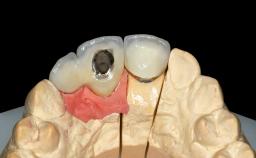

Replacement of Teeth 12 and 13 with Tissue-Level Implants

Prosthesis Type FDP

Retention Cemented, with prosthesis margin < 3mm submucosal Cemented, with prosthesis margin < 3mm submucosal

Provisional Implant-Supported Prosthesis Prosthodontic margin >3 mm apical to mucosal crest Prosthodontic margin >3 mm apical to mucosal crest